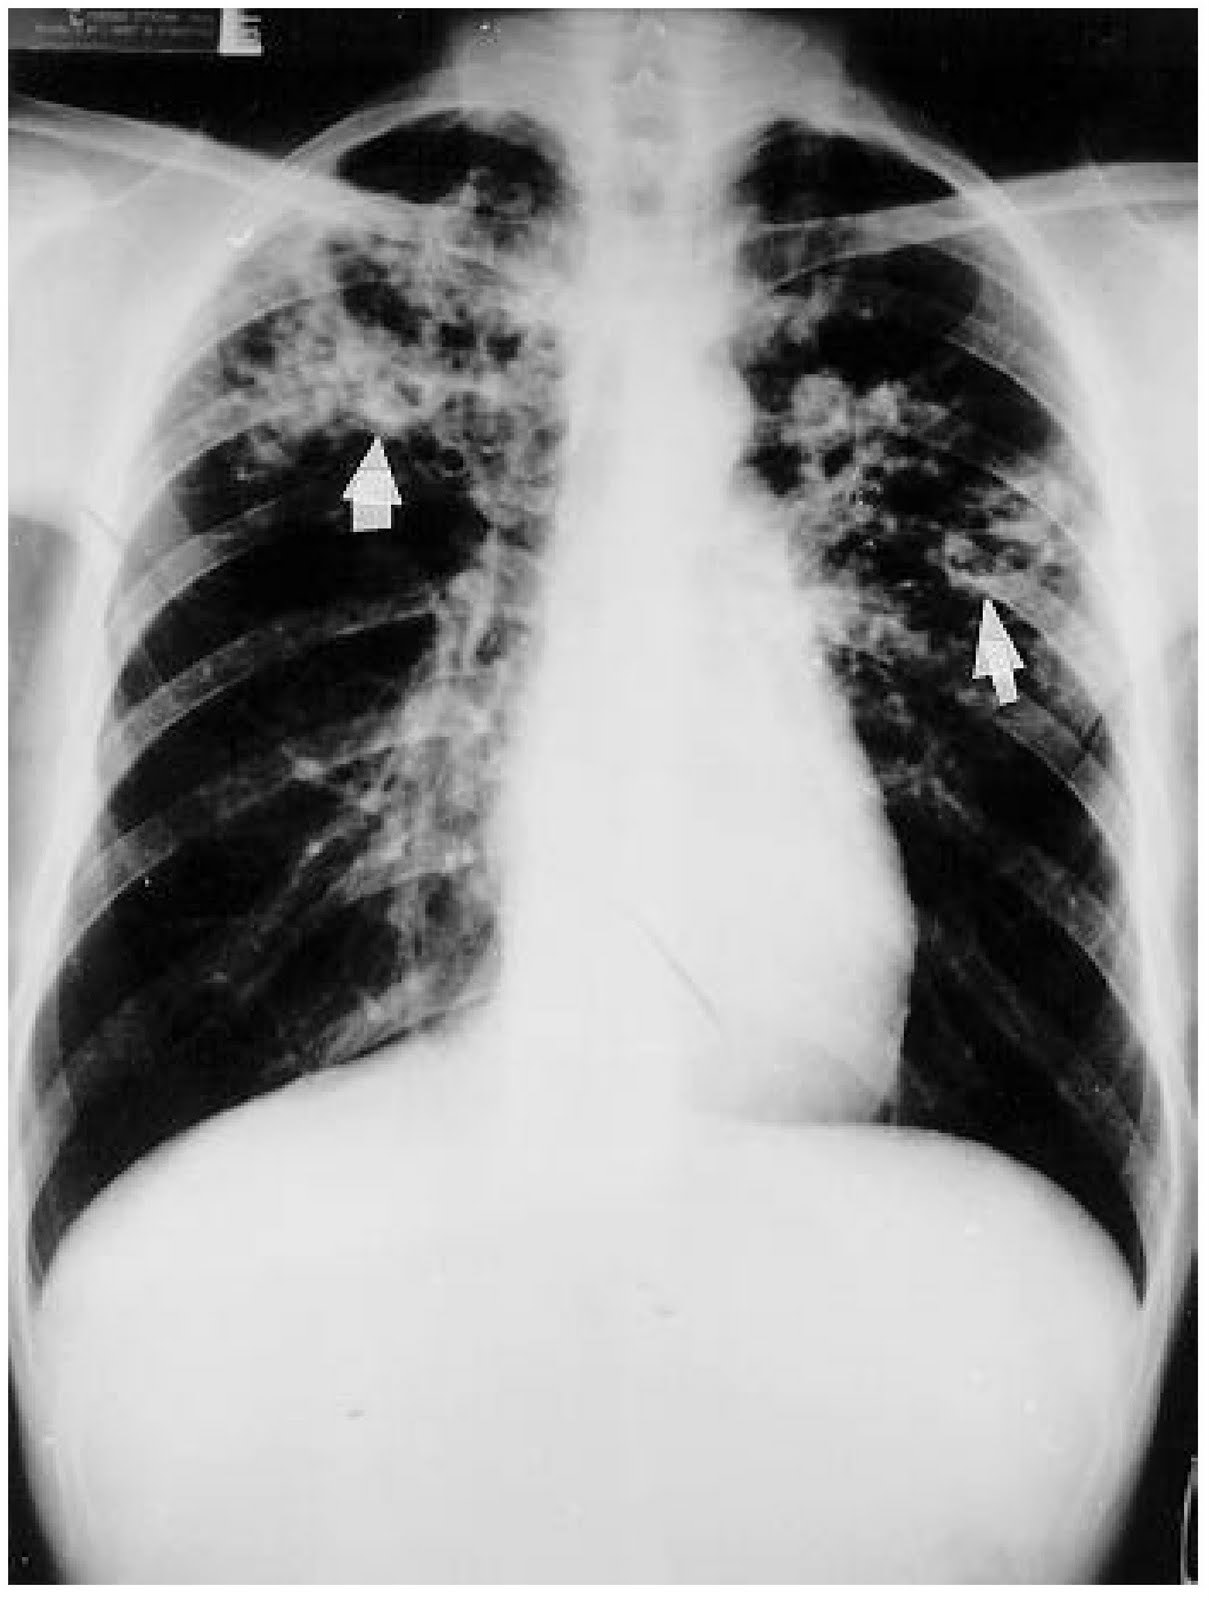

Paciente, HIV positivo, com clínica de febre, tosse, sudorese noturna, emagrecimento, sempre devemos levantar hipotese de ….

TUBERCULOSE

Agente: Mycobacterium tuberculosis

Qualquer CD4

Rx: CD4 > 350: apical, cavitário // CD4 < 350: miliar, difuso

Diagnóstico: escarro: TR ou baciloscopia, sempre cultura

Tratamento: RIPE 2m + RI 4m… TARV em até 2 sem após

Quando e como realizar profilaxia de tuberculose em paciente com AIDS?

Isoniazida 270 doses (9-12 meses)